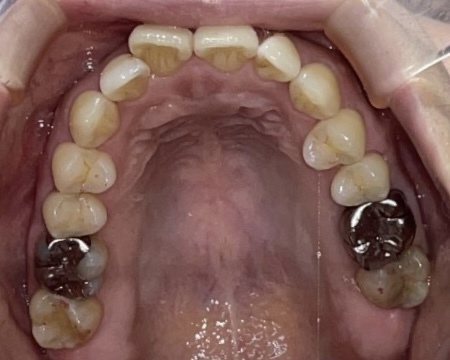

Before

After

矯正の種類 / invisalign GO

年齢・性別 / 40代女性

主訴  /  上下の叢生、開咬、オーバージェット

治療期間 / 12ヶ月

費用 / 簡易検査 5,000円(税別) 精密検査 30,000円(税別)

両額マウスピース 450,000円(税別) 両額リテイナー料 40,000円(税別)

※マウスピース交換時別途調節料5,000円(税別)

副作用 / 口内炎・歯の移動に伴う痛み・知覚過敏 ※数日で収まる場合が多いです

リスク / 後戻り防止の為、夜のみマウスピースで保定を指示